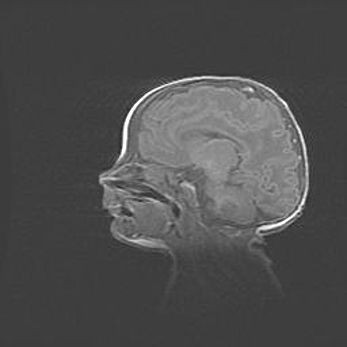

Открытая гидроцефалия.

Возраст: 6 месяцев 15 дней

Вес: 6200 г

Пол: женский

Окружность головы: 41 см

Срок гестации: 38 недель

Гидроцефалия головного мозга у новорожденных – это скопление избыточного количества цереброспинальной жидкости в головном мозге. Ее избыточное скопление в мозге приводит к патологическому расширению желудочков мозга (четырех полостей, расположенных в глубине белого вещества мозга, заполненных цереброспинальной жидкостью и связанных узкими проходами).

Открытый тип гидроцефалии (сообщающаяся) наблюдается тогда, когда нарушен механизм всасывания ликвора в системный кровоток. При этом типе причиной заболевания чаще всего является перенесенные ранее инфекции (например: менингит),  либо же наличие крови в субарахноидальном пространстве.